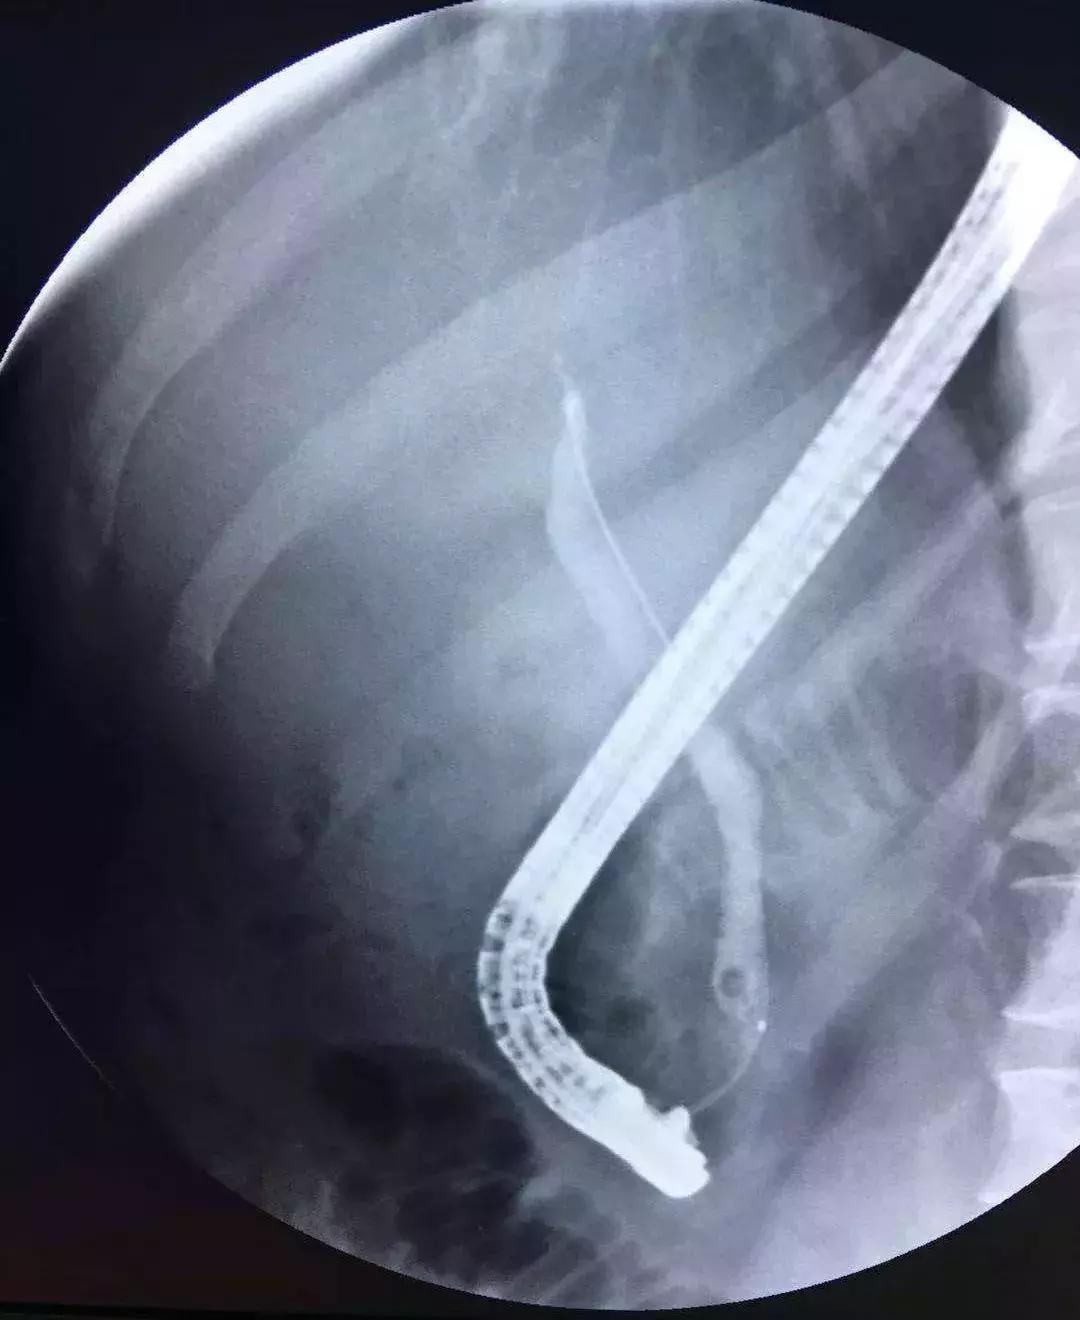

ERCP治疗

对于轻度或中度急性胆管炎伴胆管结石且无抗凝治疗或凝血功能异常的病人,可斟酌在胆管引流的同时进行内镜下括约肌切开术(EST)清除结石,但EST常见的并发症有胰腺炎、十二指肠或胆管穿孔、出血和感染等,同时切开括约肌可能造成肠液返流,将来再次诱发胆管炎,因此有些医生选择气囊扩张壶腹部再行取石,这样能保存括约肌的功能。

对取石困难的病人,如结石较大或多发结石等,能够分两次进行:先行ENBD胆管引流,待炎症得到控制后再经内镜清除结石。

PTCD治疗